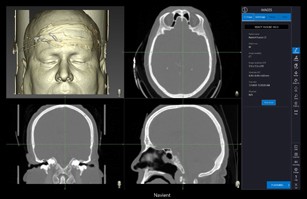

Navient’s software user interface is intuitive and simple to follow. Once data is loaded, Navient software operation proceeds sequentially through 6 stages as follows:

Images

Load CT or MRI images from USB, DVD or PACS

Image Fusion

Merge CT and MRI images (Optional)

Planning

Build 3D model of sinus (Optional)

Navigate in 3D & 2D views, Smart 3D front clip, display 3D sinus model